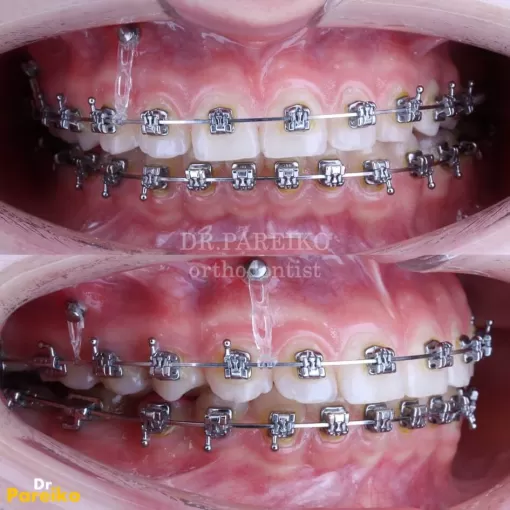

жалобы на скученность зубов на нижней челюсти и вестибулярное положение клыка на верхней челюсти справа

Стоматолог-ортодонт Парейко П.А.

Пациентка обратилась с жалобы на скученность зубов на нижней челюсти и вестибулярное положение клыка на верхней челюсти справа.